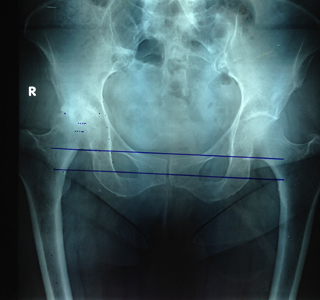

ΑΡΘΡΟΠΛΑΣΤΙΚΗ ΙΣΧΙΟΥ

Τεχνική AMIS: Η πολύ μικρή πρόσθια προσπέλαση του ισχίου υπερτερεί επειδή είναι ατραυματική (δεν υπάρχει διατομή μυών ή τενόντων) όπως συμβαίνει στις υπόλοιπες τεχνικές. Η τεχνική αυτή με το ειδικό εξάρτημα χειρισμού του σκέλους με την πολύ μικρή τομή επιτυγχάνει καλό οπτικό πεδίο προσπέλασης. Σπάνια χρειάζεται μετάγγιση αίματος, η νοσηλεία είναι σύντομη (1-2 ημέρες) ενώ η βάδιση με μερική φόρτιση είναι άμεση. Ο πόνος είναι ελάχιστος και στο μεγαλύτερο αριθμό των ασθενών ανεπαίσθητος.

| Προεγχειρητική | Μετεγχειρητική |